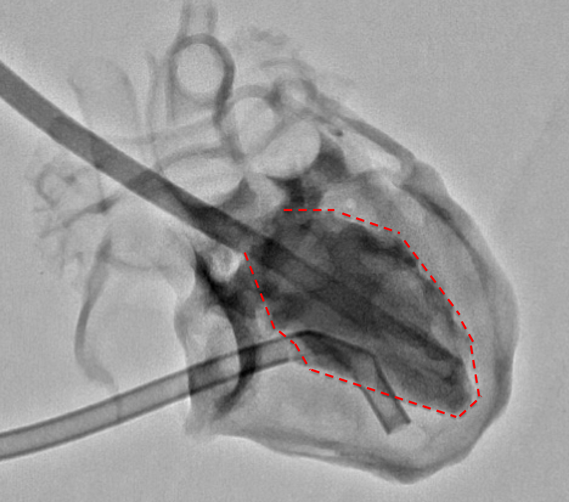

During Cath, ventricular imaging was performed from two directions: the postero-anterior and left lateral directions (Fig. 2a). Then, the ventricular volume was measured using Cardio Agent analysis software (Toshiba Medical Systems Corporation, Tochigi, Japan), where the left ventricular volume was measured using the area-length method and the right ventricular volume was measured using the Graham method. The images of the left and right ventricular chamber were traced in places where the shading is clear.

Fig. 2a The image of cardiac catheterization

The postero-anterior view of left ventricular angiography in ASD model. The dotted line shows the traced line. ASD: atrial septal defect